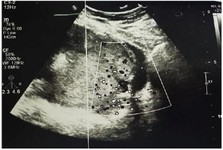

At 29 weeks of gestation, the patient experienced a mild vaginal bleeding episode and was admitted to Imam Reza Hospital. Ultrasound confirmed persistent placenta percreta (Figure 2). Vital signs were stable. She received neuroprotective magnesium sulfate and two doses of betamethasone for fetal lung maturity. After 72 hr, the bleeding resolved, and she was discharged with instructions for close monitoring and immediate return if symptoms recurred.

Figure 2. Ultrasound image demonstrating loss of interface between the myometrium and placenta, with increased vascularity behind the placenta and presence of multiple placental lakes, consistent with placenta percreta